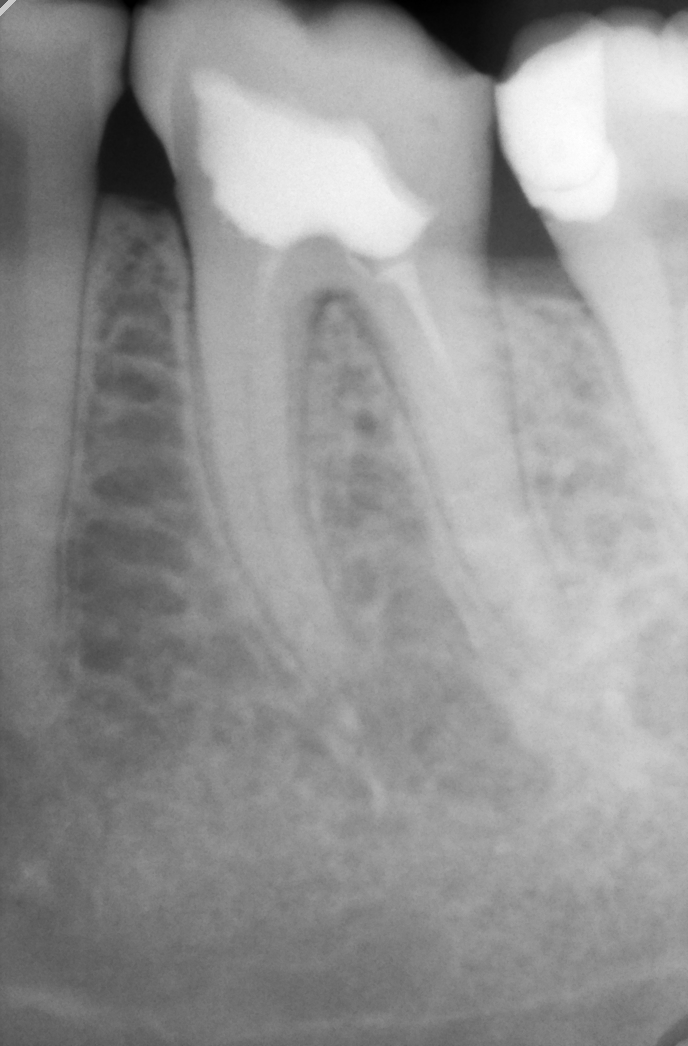

- zub.png (380.03 KiB) Прегледано 652 пъти

преди 6 месеци ми умъртвиха зъб. Още след поставянето на пломбата макар и рядко усещам дискомфорт ( споделяла съм за това със стоматолога ) - моментна остра болка, обикновено при по-твърда храна, но преди 2 дни през нощта ми се появи и една тъпа болка за час, два и отмина. Но като цяло усещам дискомфорт с този 6 долен ляв зъб.

Веднага си направих снимка и отидох при стоматолога, който ми беше поставил пломбата. Обясни ми, че не е страшно - имало размекване на пломбата, но ми предписа антибиотик и ми назначи час след 15 дни?!? Искам също така да кажа, че съм споделяла за дискомфорта 2-3 пъти през тези месеци, но не ми беше назначена снимка и за това сега реших да си направя такава.